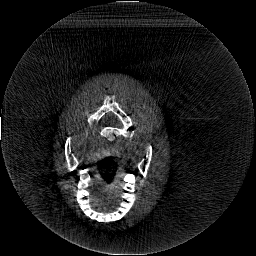

Krylov subspace methods are a powerful family of iterative solvers for linear systems of equations, which are commonly used for inverse problems due to their intrinsic regularization properties. Moreover, these methods are naturally suited to solve large-scale problems, as they only require matrix-vector products with the system matrix (and its adjoint) to compute approximate solutions, and they display a very fast convergence. Even if this class of methods has been widely researched and studied in the numerical linear algebra community, its use in applied medical physics and applied engineering is still very limited. e.g. in realistic large-scale Computed Tomography (CT) problems, and more specifically in Cone Beam CT (CBCT). This work attempts to breach this gap by providing a general framework for the most relevant Krylov subspace methods applied to 3D CT problems, including the most well-known Krylov solvers for non-square systems (CGLS, LSQR, LSMR), possibly in combination with Tikhonov regularization, and methods that incorporate total variation (TV) regularization. This is provided within an open source framework: the Tomographic Iterative GPU-based Reconstruction (TIGRE) toolbox, with the idea of promoting accessibility and reproducibility of the results for the algorithms presented. Finally, numerical results in synthetic and real-world 3D CT applications (medical CBCT and {\mu}-CT datasets) are provided to showcase and compare the different Krylov subspace methods presented in the paper, as well as their suitability for different kinds of problems.